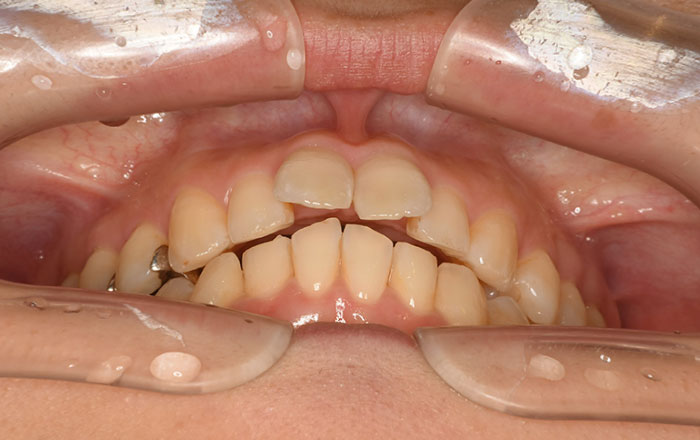

今回は、お子さんの歯並びに悪影響を与える、6つの悪癖についてご紹介します。

乳歯がむし歯などで歯が折れてしまったり、頭の部分がなくなってしまうと、両隣の歯が倒れかかってしまったり、噛み合っているはずの対の歯が出てきてしまったり、歯並びにも影響します。

両隣の歯が倒れかかってしまうと、永久歯が生えるだけのスペースがなくなり、永久歯が変な方向から生えて、歯並びが悪くなってしまいます。